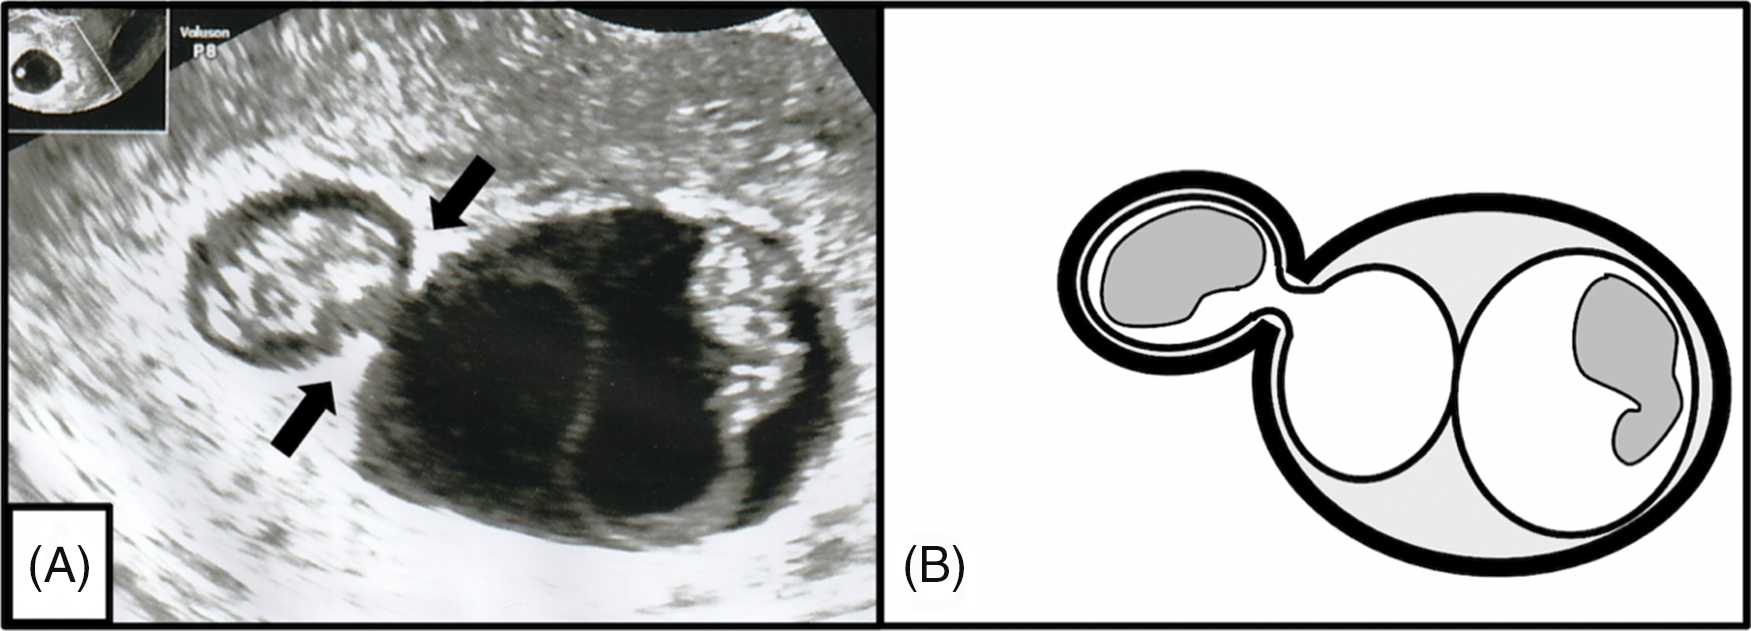

A 32-year-old woman, gravida 2 para 0, was referred to our institution at 7 weeks of gestation. Transvaginal ultrasonography identified two GSs, suggesting a dichorionic twin pregnancy, and two embryos with fetal heartbeats (Figure 1).

Fig. 1. Two gestational sacs and two embryos with heartbeats were observed at 7 weeks’ gestation.

At 9 weeks’ gestation, an ultrasound image showed a lambda sign composed of thick triangular tissues without consecutive membranes from both sides, resulting in the diagnosis of an MCDA twin pregnancy with chorionic membrane folding (CMF; Figure 2A). Figure 2B shows a graphic representation of the ultrasound image.

Fig. 2. (A) Lambda signs were detected on both sides of the base of the intertwin membrane at 9 weeks’ gestation. An amniotic membrane swelled toward one side between the chorionic membrane folding (arrows). (B) A graphic representation of the ultrasound image.

To the best of our knowledge, this is the first case report that demonstrates changes in ultrasound findings during a monochorionic pregnancy with CMF. This report describes two important ultrasound chorionicity findings: monochorionic pregnancies with CMF can show two GSs and a lambda sign and the CMF can flatten or change during the pregnancy.

Before 10 weeks’ gestation, the relationship between the number of GSs and the number of embryonic heartbeats provides a strong indication of chorionicity (Morin & Lim, Reference Morin and Lim2017). The presence of two GSs is strongly believed to indicate a dichorionic twin pregnancy, but the presented monochorionic twin pregnancy case also showed two GSs. This is consistent with a previous case report of a monochorionic twin pregnancy with two GSs in the first trimester and is complicated by TTTS (Yamashita et al., Reference Yamashita, Ishii, Hidaka, Hayashi, Takeuchi and Mitsuda2015). The presence of CMF from the base of the intertwin membrane suggests that the chorionic membranes were very close to each other, mimicking two GSs early in the first trimester.

The lambda sign, also called as the twin peak sign, is a triangular tissue projection extending from the base of the intertwin membrane consisting of chorionic tissue between two amniotic membranes (Finberg, Reference Finberg1992). A recent meta-analysis showed that the presence of the lambda sign was very sensitive and specific in predicting chorionicity during ultrasonography in the first trimester (Maruotti et al., Reference Maruotti, Saccone, Moriando and Martinelli2016). Generally, the presence of the lambda sign indicates a dichorionic twin pregnancy. In this case, ultrasonography performed at 9 weeks’ gestation detected the lambda sign on both sides of the base of the intertwin membrane and amniotic membrane swelling between the two chorionic membranes. This finding supports the concept that CMF can show the lambda sign and that the form of CMF can change during pregnancy. The difference in the lambda sign between dichorionic monoamniotic (DCDA) twin pregnancies and MCDA twin pregnancies is that the triangular tissue projection extending from the base of the intertwin membrane is followed by a relatively thick membrane to the other side in DCDA twin pregnancies, whereas the CMF in MCDA twin pregnancies does not follow chorionic membrane from the lambda sign and the thick chorionic membrane appears to be interrupted.